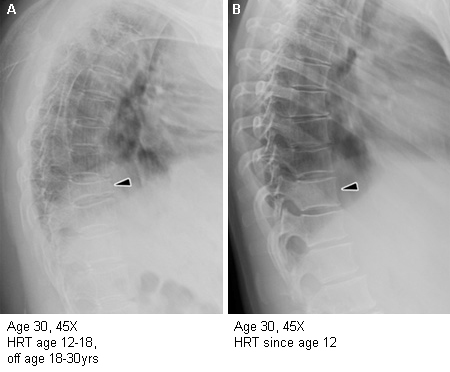

Importance of oestrogen therapy in young adults with Turner syndrome (TS): X-ray figure A shows near collapse of T11, diffuse osteoporosis, and dorsal kyphosis in a woman with TS who discontinued HRT at age 18 years. Figure B shows normal spinal architecture and bone health in another woman with TS, age 30 years, who has taken HRT consistently since age 12.8 years

From the personal collection of Carolyn Bondy, MS, MD (NIH study)